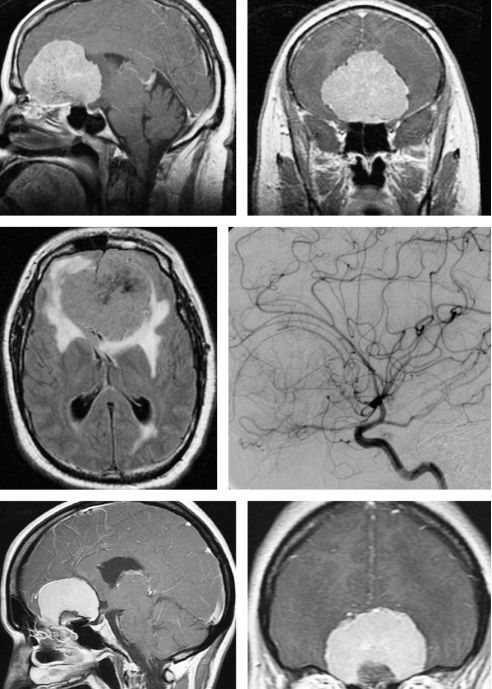

图3. 巨大嗅沟脑膜瘤(上排、中排)及周围明显水肿。注意额极的位移和血管造影上大脑前动脉情况。此肿瘤适于进行经颅入路切除。如果肿瘤在MRI上没有明显超过眶中线或视神经外侧,则可以使用经鼻入路(下排)。